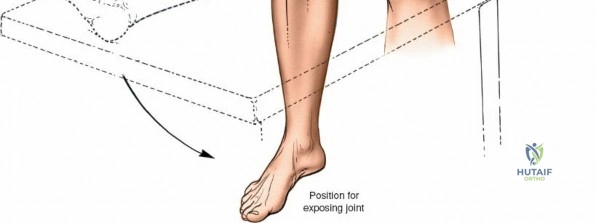

Patient Positioning

- Supine Position: The patient is positioned supine on the operating table. This allows for excellent access to the anterior aspect of the knee.

- Leg Holder vs. Free-Draping:

- Leg Holder: Often used in TKA to stabilize the femur and allow controlled flexion and extension during bony resections and gap balancing.

- Free-Draping: If a leg holder is not used, the foot of the table is typically dropped to allow full knee flexion. The limb is often draped free (e.g., using a stockinette and impervious drape) to permit manipulation of the knee through a full range of motion, which is crucial for assessing stability, patellar tracking, and implant fit, especially in revision cases or for fracture fixation.

- Sterile Preparation and Draping: The entire leg, from the tourniquet to the toes, is meticulously prepared with an antiseptic solution (e.g., povidone-iodine or chlorhexidine) and then sterilely draped to isolate the operative field.

- Patellar Position: The knee should be slightly flexed (15-30 degrees) or in full extension initially to facilitate the skin incision. Adjustments will be made throughout the procedure. Adequate padding for the heels, sacrum, and upper extremities is crucial to prevent pressure injuries. The ipsilateral hip may be slightly abducted and externally rotated for optimal surgical field ergonomics.